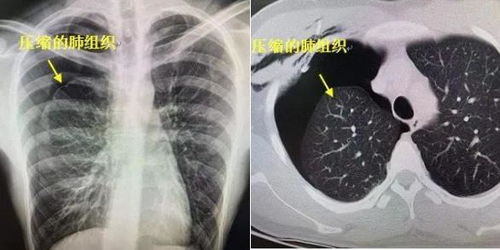

突然出現(xiàn)胸痛、呼吸困難應(yīng)立即到醫(yī)院做X線檢查,胸片上顯示無肺紋理的均勻透亮區(qū)的胸膜腔積氣帶,其內(nèi)側(cè)為弧形的線狀肺壓縮邊緣,可確診稱為氣胸。但有其他一些急癥也有類似表現(xiàn),如急性心肌梗塞、急性肺栓塞、肺大皰、急腹癥等,如果X線檢查未見氣胸征象,應(yīng)立即做進(jìn)一步檢查以明確病因,如心電圖等。